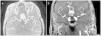

Se realiza una angio-RMN (resonancia magnética nuclear), sin contraste por su insuficiencia renal avanzada, y en ella se observa la presencia de un aneurisma sacular gigante de 19 x 16 mm en la arteria comunicante anterior (figura 1 y figura 2). Se decide tratamiento conservador, dado que los segmentos distales de las arterias cerebrales anteriores (ACA) salen del propio aneurisma y, si se emboliza o se clipa, se produciría isquemia de los territorios irrigados por las ACA.

Figura 2. Angio-resonancia magnética nuclear máxima intensidad del pixel (MIP) axial y coronal